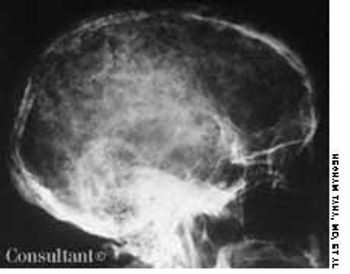

Bullet in the Brain

ByGamil Kostandy, MD,Hesham Taha, MD,Salama Salama, MD,Maged Ghaly, MD,Bruce Sosler, MD,Hani Ashamalla, MD While evaluating this 26-year-old man for suspected sinusitis, skull films revealed the fragments of a 32-caliber gunshot embedded in his brain. The anteroposterior and lateral radiographs show three metallic bullet fragments; the largest remnant is on the left side of the occipitoparietal region. The patient reported being shot at age 11 but denied any residual neurologic signs.